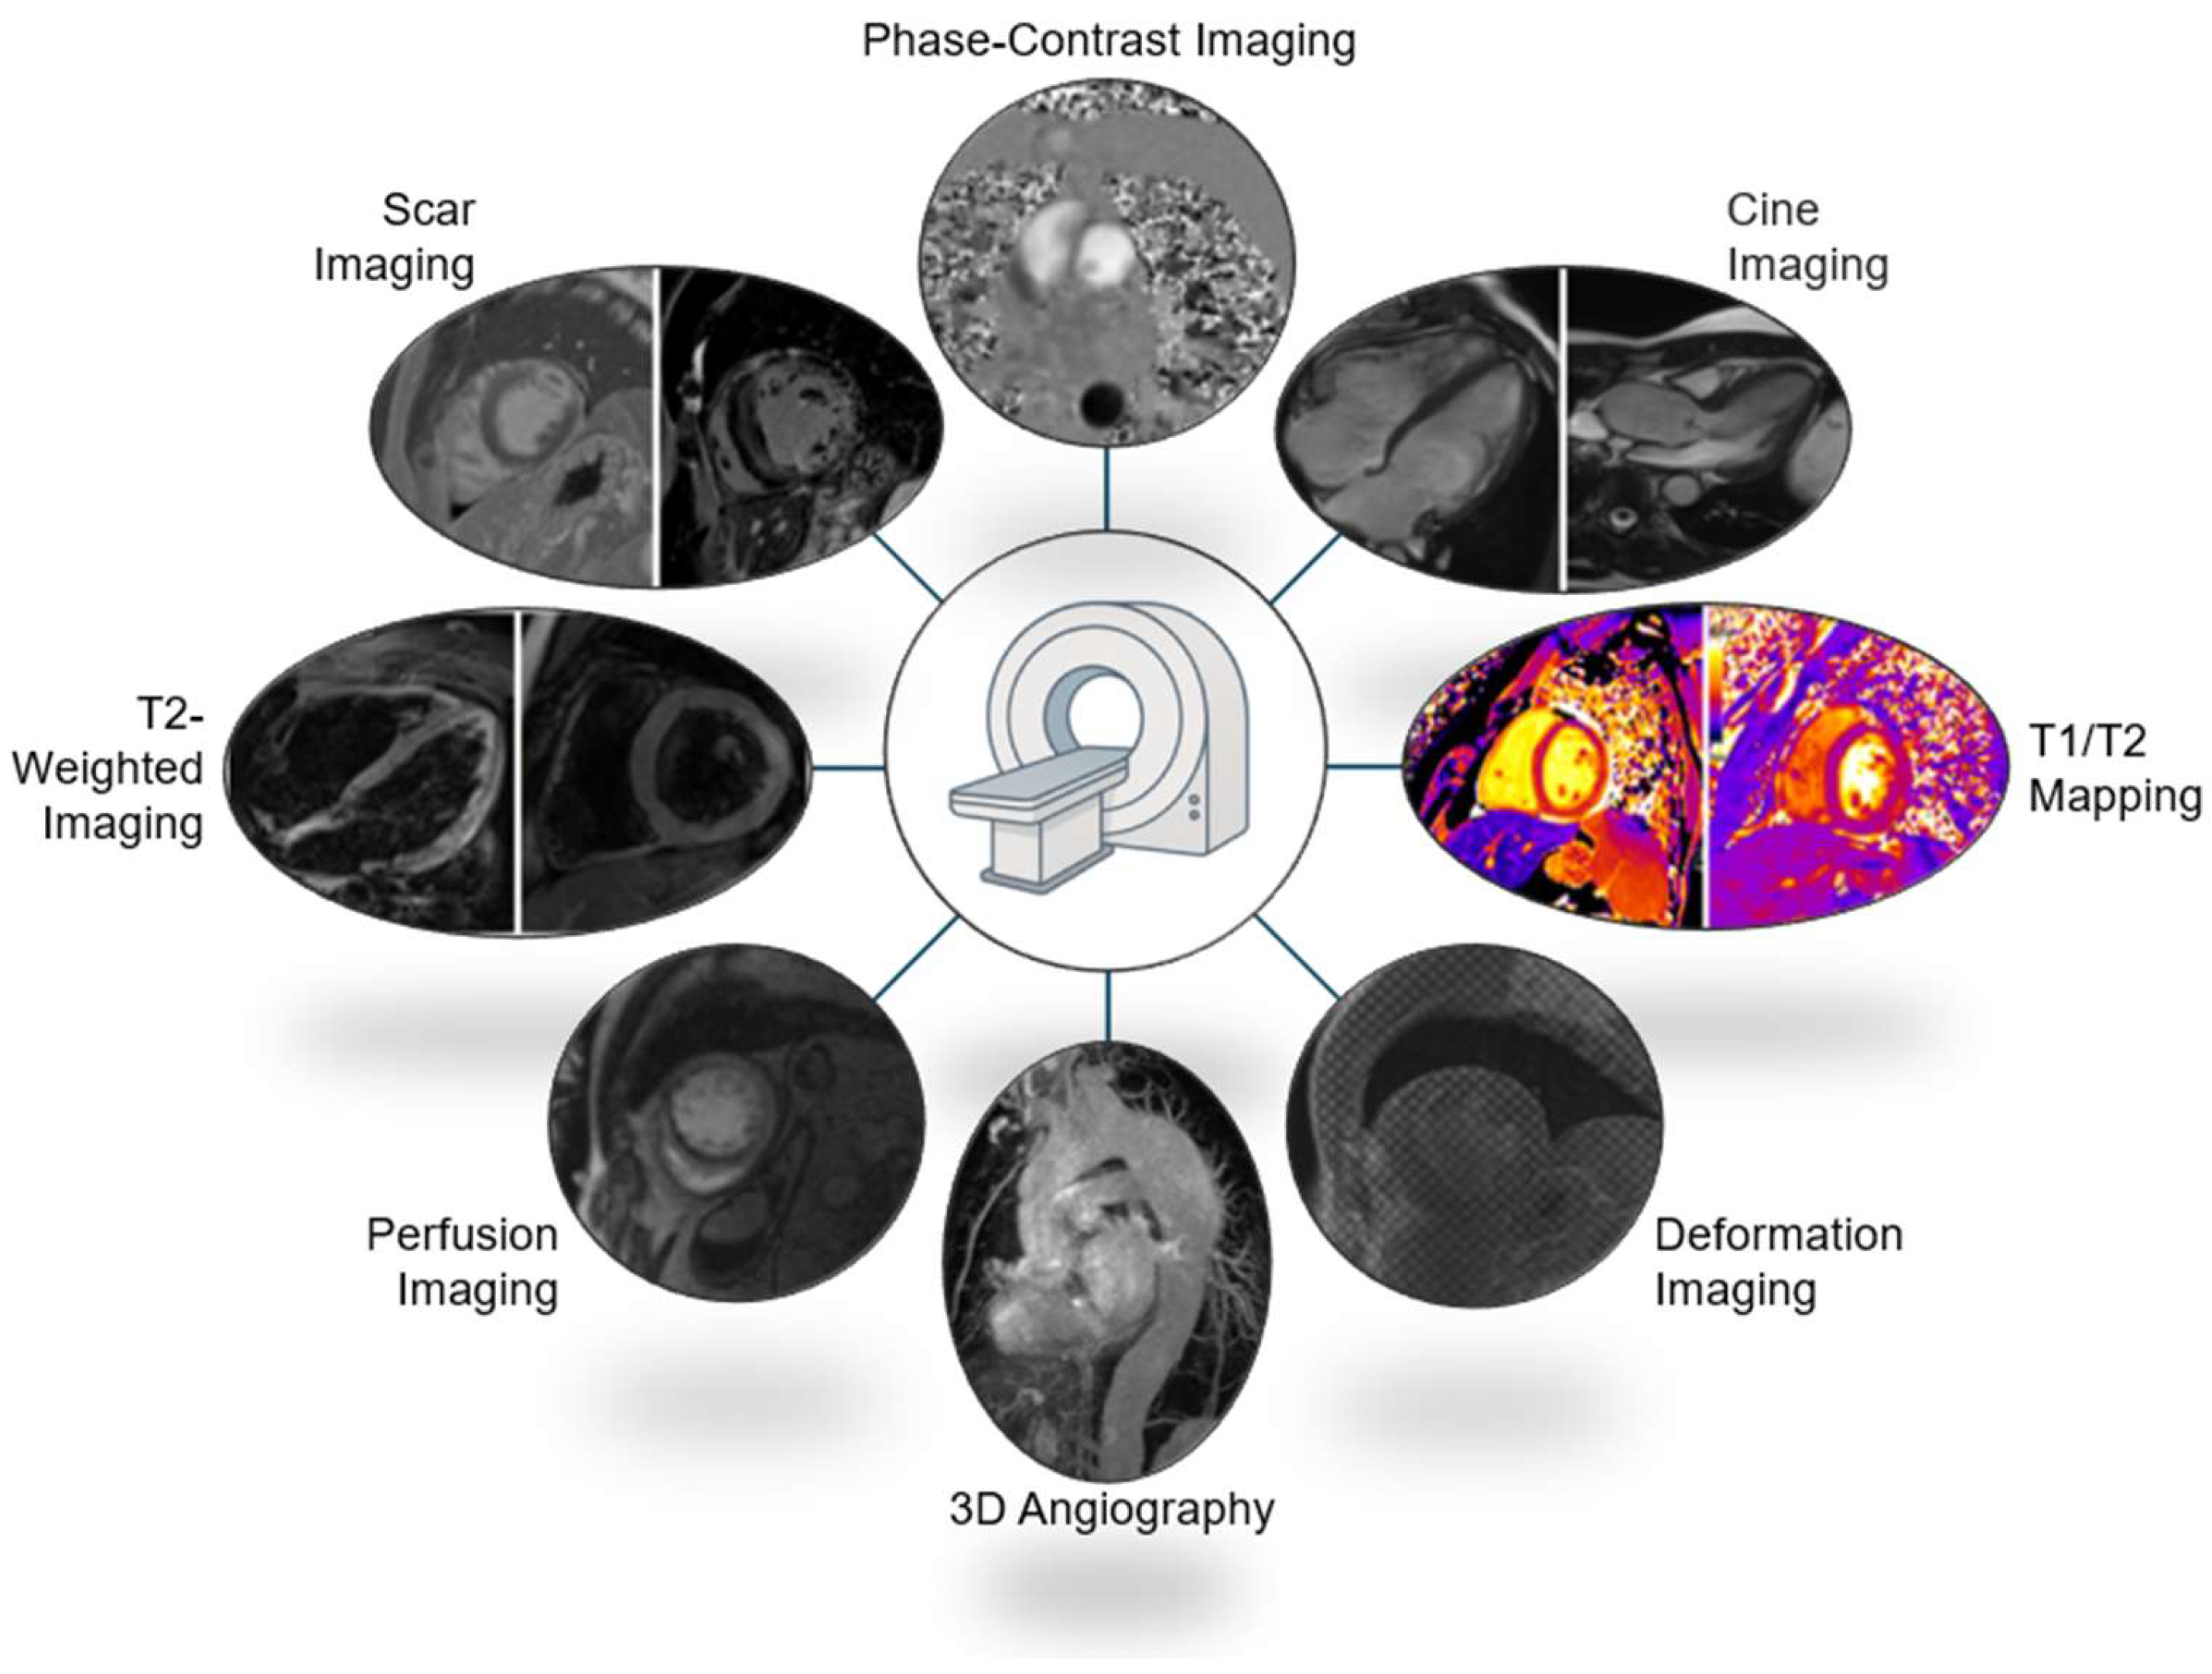

2. Clinical Indications for Cardiac MRI in Athletes

3.6. Cardiac MRI Protocols